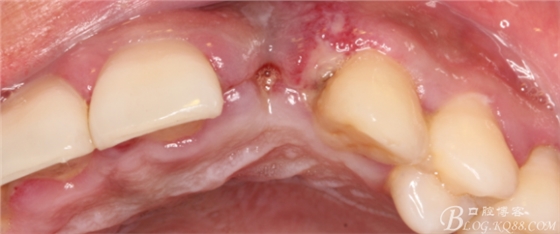

于是我果斷告知患者,手術(shù)失敗了,不能拖延,如不及時(shí)處理,炎癥繼續(xù)發(fā)展會(huì)很快波及鄰牙牙槽骨。患者接受我的建議。切開翻瓣,骨粉及生物膜消失了,骨吸收嚴(yán)重,幸運(yùn)的是,因?yàn)樘幚砑皶r(shí),鄰牙骨支持依然存在。